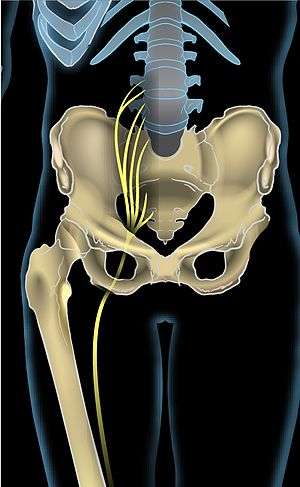

Anterior view showing the sciatic nerve going down the right leg | |